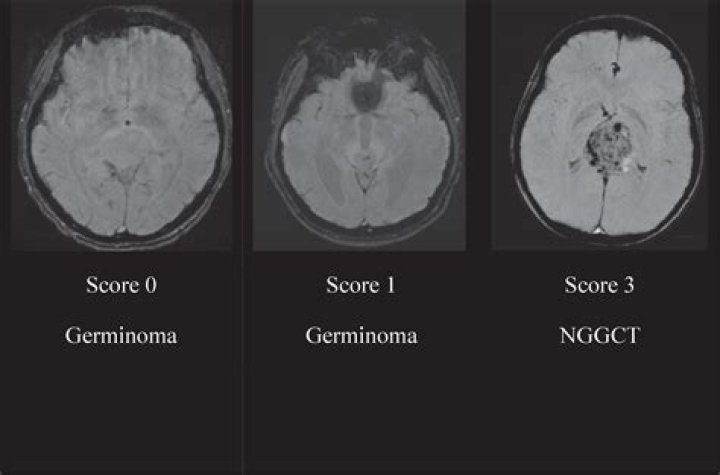

What is a pineal germinoma?

A type of germ cell tumor that is found in the pineal gland in the brain. Symptoms of pineal germinomas include headaches, changes in vision, nausea, and vomiting.